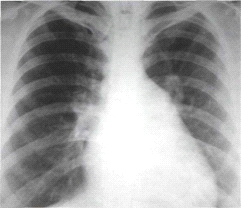

Рис.2. Рентгенограмма сердца в переднезадней проекции больного с митральным стенозом. Митральная конфигурация сердца